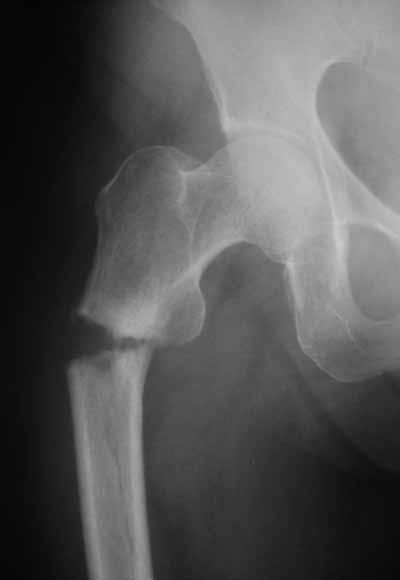

Да? Качество рентгенограмм конечно неочень, но ведь это нестабильный перелом 31.А2.2, не так ли?

Не думаю так. см вложение.

> Да? Качество рентгенограмм конечно неочень, но ведь это